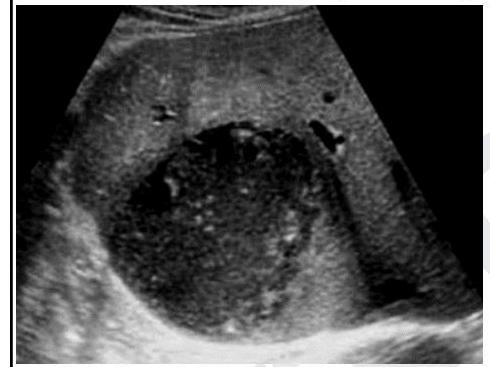

A 40-year-old man visits the office with complaints of fever and abdominal pain for the past 6 days. He is also concerned about his weight loss as he weighs 3.6 kg (8 lb) less, today, than he did 2 months ago. He has a previous history of being admitted to the hospital for recurrent cholangitis. The vital signs include: heart rate 97/min, respiratory rate 17/min, temperature 39.0°C (102.2°F), and blood pressure 114/70 mm Hg. On physical examination, there is tenderness on palpation of the right upper quadrant. The laboratory results are as follows: Hemoglobin 16 g/dL Hematocrit 44% Leukocyte count 18,000/mm3 Neutrophils 60% Bands 4% Eosinophils 2% Basophils 1% Lymphocytes 27% Monocytes 6% Platelet count 345,000/mm3 Aspartate aminotransferase (AST) 57 IU/L Alanine aminotransferase (ALT) 70 IU/L Alkaline phosphatase 140 U/L Total bilirubin 8 mg/dL Direct bilirubin 5 mg/dL An ultrasound is also done to the patient which is shown in the picture. What is the most likely diagnosis?

Explanation: ***Liver abscess*** - The patient presents with **fever**, **RUQ tenderness**, **leukocytosis**, and a **history of recurrent cholangitis**, which increases the risk of pyogenic liver abscess formation. - The ultrasound would likely show a **fluid-filled lesion** in the liver, consistent with an abscess. *Hepatitis B* - While hepatitis B can cause **fever, abdominal pain, and liver enzyme elevation**, it typically does not present with a discrete mass or recurrent cholangitis. - The provided symptoms and lab results are more indicative of an **infectious process with focal involvement**. *Acute cholecystitis* - This condition involves **inflammation of the gallbladder**, usually due to gallstones, presenting with RUQ pain, fever, and leukocytosis. - However, the patient's **recurrent cholangitis history** and the high bilirubin levels suggest obstruction or infection within the bile ducts or liver parenchyma, rather than just gallbladder inflammation. *Cholangitis* - Cholangitis is an **infection of the bile ducts**, characterized by **fever, RUQ pain, and jaundice** (**Charcot's triad**), which matches many of the patient's symptoms. - However, the question states a history of recurrent cholangitis, and the current presentation, especially with the high leukocytosis and potential for a focal lesion on ultrasound, points towards a **complication of chronic cholangitis**, such as a liver abscess. *Hepatocarcinoma* - Hepatocarcinoma typically presents with **weight loss, abdominal pain, and an elevated alpha-fetoprotein level**, but fever is usually not as prominent unless there's tumor necrosis or infection. - The **acute febrile presentation** and marked leukocytosis are more consistent with an infectious process rather than a malignancy.